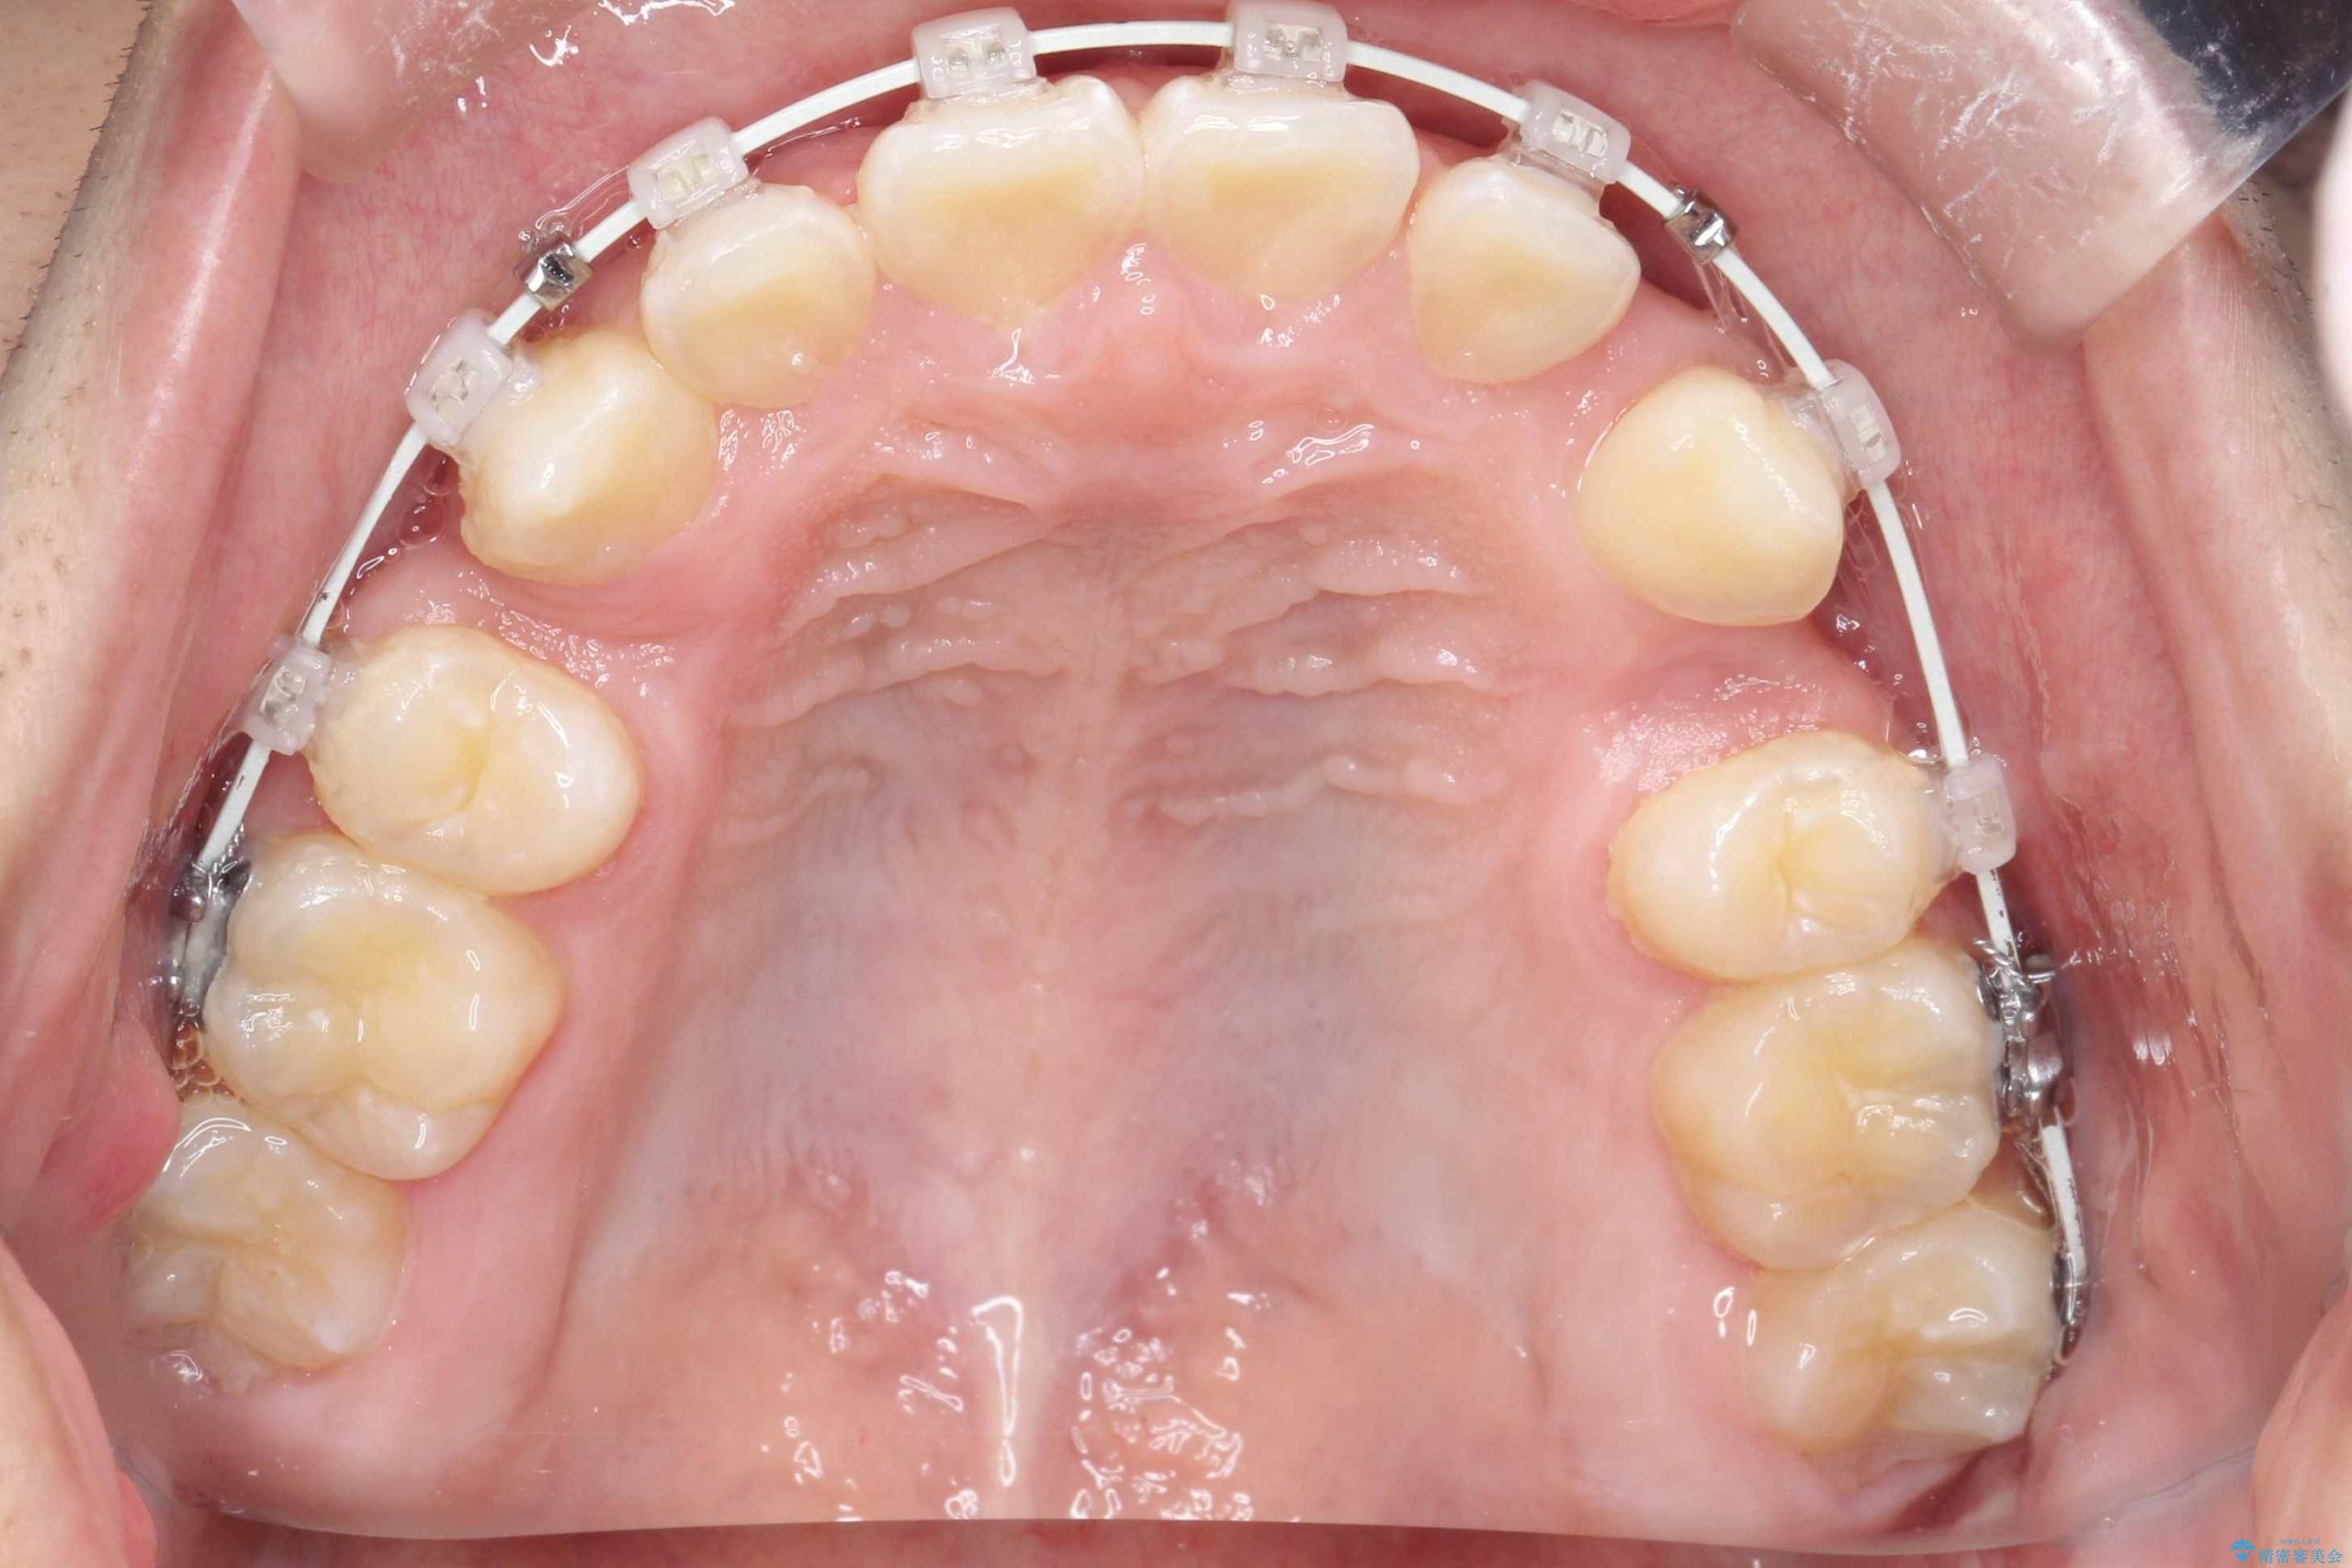

- ワイヤー(審美装置)

矯正の精密検査の結果上顎左右4番の計2本を抜歯し、審美性に配慮したワイヤー矯正装置(審美装置)を用いて治療を行いました。